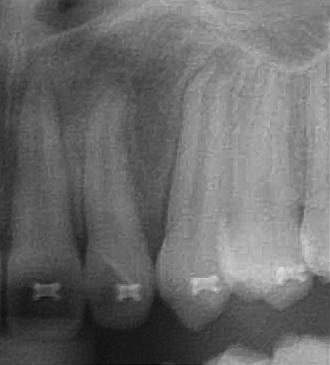

患者陳小妹妹(治療時僅9歲),於本院接受齒顎矯正治療,經數位X光(圖二)診斷,左側乳犬齒之上尚有埋伏的恆牙犬齒為假牙,使用口內攝影(圖二)與病患解釋,建議患者處理方式如下:

圖二 |